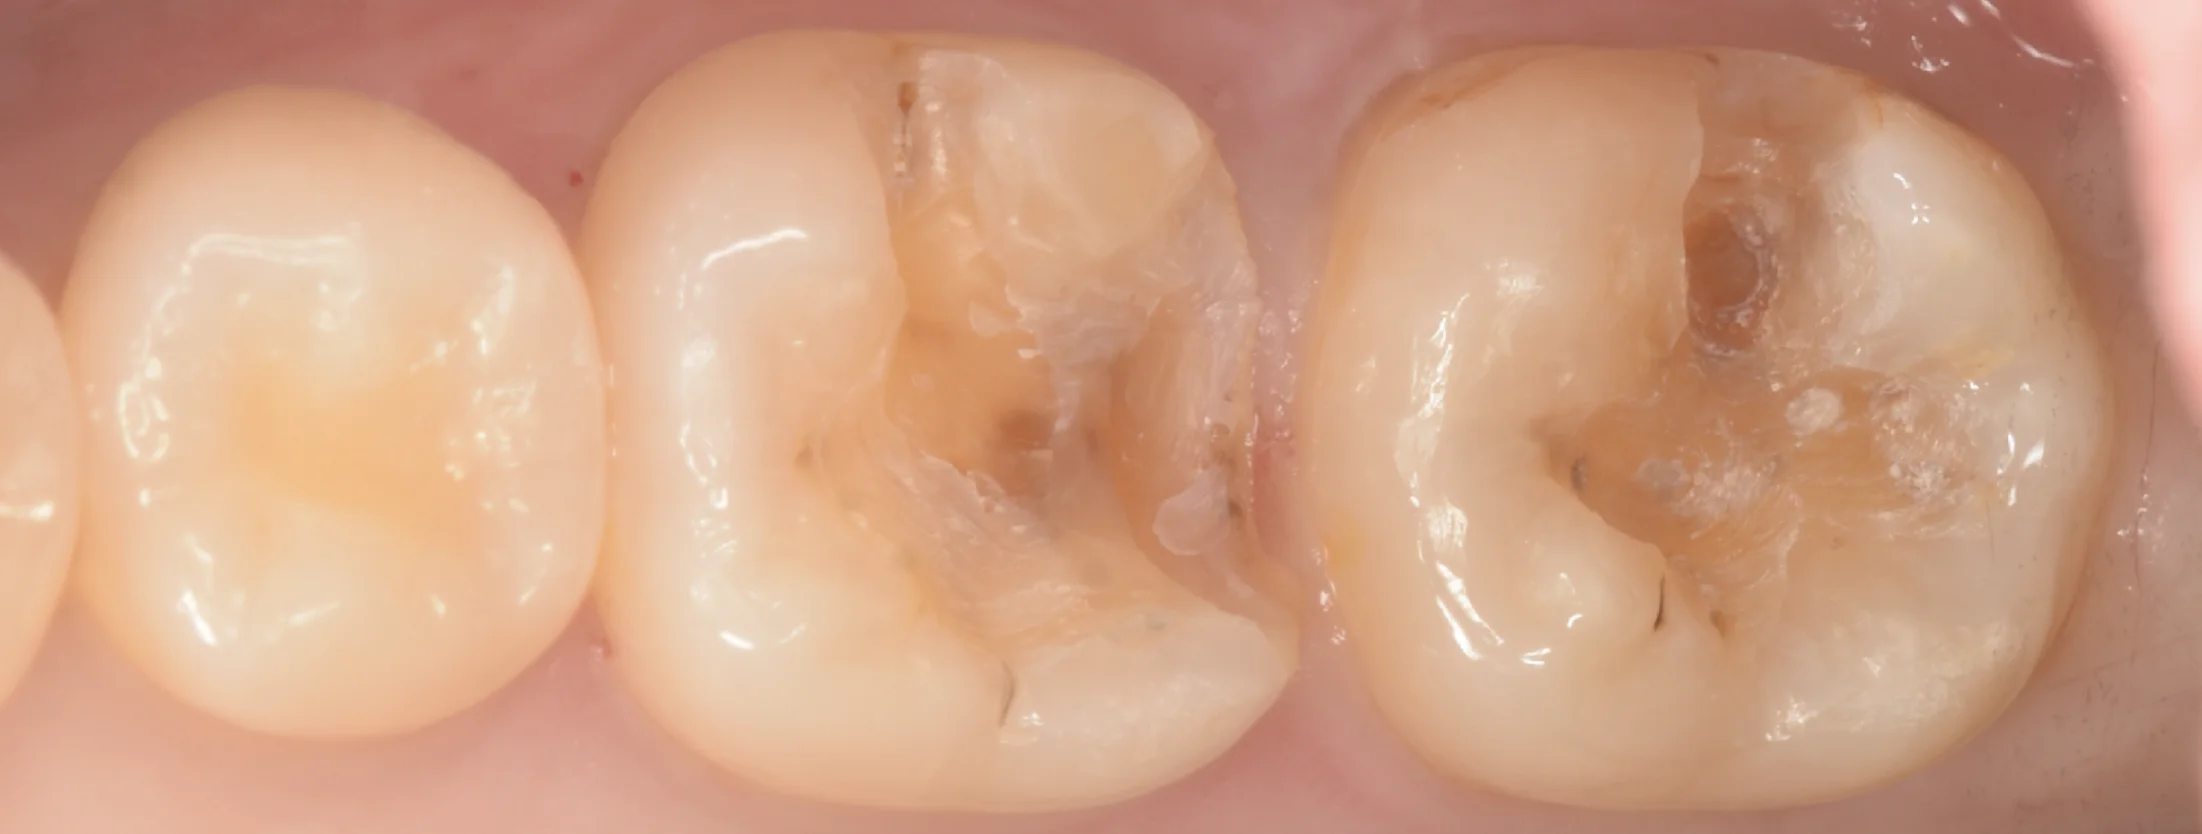

まずは術前からです。

術前

2〜3年ほど前に入れたCAD/CAMインレーと呼ばれるものが入っています。

前回同様、一部が欠けていますね。

これも前回と全く一緒の物言いになりますが…

2022年に保険適用となった治療法ですが・・・正直いって・・・予後は非常に悪いです。